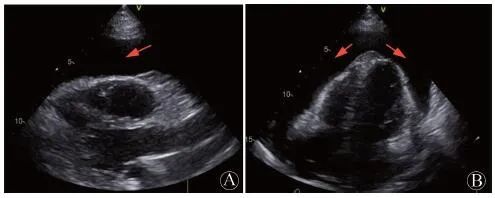

患者行TEE提示右心房及心包内可见多处中低回声团块影,最大位于近右房室沟,大小约49 mm×25 mm,其内血流丰富,并再次观察TTE,在非标准切面显示右房占位(图2 )。考虑肿瘤性病变可能性大。胸部增强CT见右心部分心包增厚,右心房、房间隔多发富血供占位,部分明显强化,部分成分强化不明显,不除外血栓形成(图3 )。PET/CT躯干断层显像:右心房增大,形态欠规则,密度不均匀,右心房、右心室及相邻心包脂肪间隙代谢不均匀异常增高,SUVmax 11.9,不除外恶性病变可能;T2椎体左后方肌间隙代谢增高灶,SUVmax 5.3,性质待定。颈胸椎旁肌肉MR增强及DWI成像均未见异常。

RV:右心室;LV:左心室;RA:右心房;LA:左心房。A:体表超声:标准心尖四腔心切面,右心房占位不明显;B:体表超声:非标准四腔心切面,可见右心房靠近房室沟部位团块性占位(箭头所示);C:TEE:非标准右心切面,可见右心房占位,其内回声不均匀(箭头所示)

图2 患者2019年11月5日超声心动图